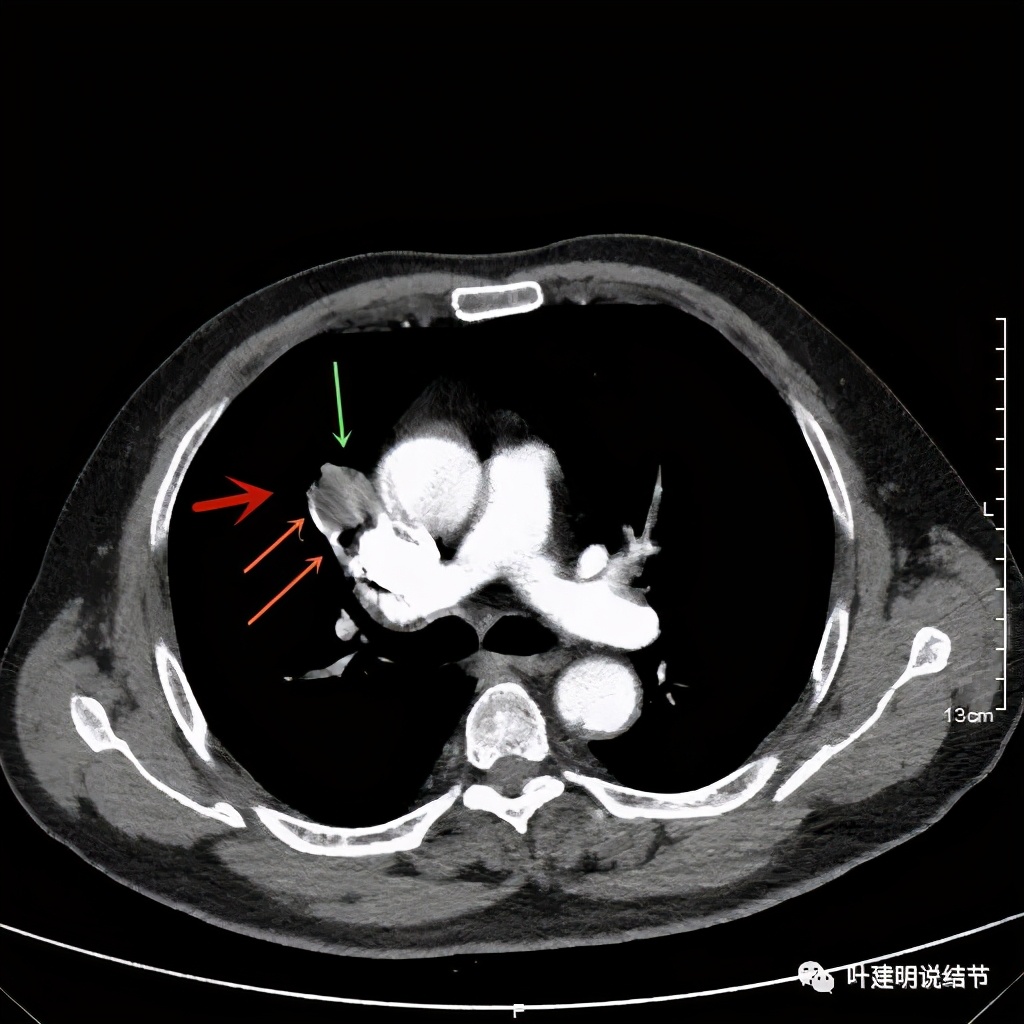

上图示病灶密度不均,但边缘过于光滑(绿色);支气管似有截断(粉色);局部有点状钙化(蓝色)

上图也示病灶密度不均,但边缘过于光滑(绿色);支气管似有截断(粉色);局部有点状钙化(蓝色)

病灶在上图层面似见支气管也是贴壁的。那么增强后又是如何呢?